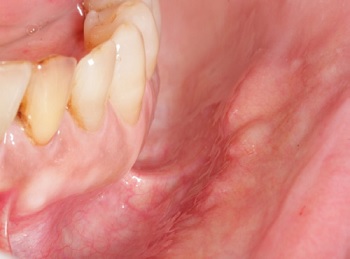

A 62-year-old Caucasian woman sought dental care complaining of the sudden growth of a “lump on the upper lip” accompanied by pain, which had appeared four weeks before the consultation. During the anamnesis, she reported a medical history of hypertension, left mitral valve hypertrophy, and hyperlipidemia, using acetylsalicylic acid, simvastatin, valsartan, and atenolol for disease control. The patient also mentioned that, shortly before the consultation, the lesion had discharged a thick yellowish exudate. Concerned about the progression of her condition, she self-medicated with azithromycin 500 mg, taking one tablet daily for three days. In addition to the aforementioned lesion (Figure 1), the intraoral examination revealed multiple submucosal nodules with a color similar to the adjacent mucosa and approximately 9.0 mm in diameter that were mobile, slightly painful, firm to palpation, and diffusely distributed across the upper and lower labial mucosa, as well as the buccal mucosa. Some displayed dilated openings that discharged mucus upon pressing (Figures 2,3, 4, and 5).

Figure 1. Clinical aspect of the lesion that prompted the complaint. A marked dilation of the ductal orifice is observed, with slight protrusion of the adjacente mucosa.

Figure 2. Clinical aspect of the nodules distributed on the right side of the upper lip.

Figure 3. Clinical aspect of the nodules distributed on the left buccal mucosa.

Figure 4. Clinical aspect of the nodules distributed on the right side of the lower lip. Discrete points of ductal dilation are observed in some of the nodules.

Figure 5. Clinical aspect of the nodules distributed on the left side of the lower lip. Discrete points of d

The lesions in our case exhibited clinical characteristics similar to those described in the previous reports, presenting as sessile nodules, firm to palpation, with coloration resembling the adjacent mucosa, sometimes with dilated openings discharging mucus, located on the buccal and labial mucosa of elderly individuals.

Although pain is uncommon, sensitivity may occur and become intense with MSGs infections,4 as seen here and in one of Tal et al.’s cases4 (Table 2). Individually, these aspects do not differ significantly from the clinical presentation of single SDC lesions.2, 4, 5 However, the unusual occurrence of multiple nodules with mucus discharge and widespread distribution across the labial and buccal mucosa may complicate identification when compared to other lesions with similar characteristics.